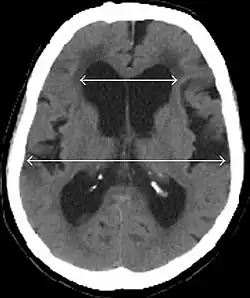

Normal pressure hydrocephalus (NPH), also called malresorptive hydrocephalus, is a form of communicating hydrocephalus in which excess cerebrospinal fluid (CSF) builds up in the ventricles, leading to normal or slightly elevated cerebrospinal fluid pressure. The fluid build-up causes the ventricles to enlarge and the pressure inside the head to increase, compressing surrounding brain tissue and leading to neurological complications. Although the cause of idiopathic (also referred to as primary) NPH remains unclear, it has been associated with various co-morbidities including hypertension, diabetes mellitus, Alzheimer's disease, and hyperlipidemia.[1][2][3] Causes of secondary NPH include trauma, hemorrhage, or infection.[4] The disease presents in a classic triad of symptoms, which are memory impairment, urinary frequency, and balance problems/gait deviations (note: use of this triad as the diagnostic method is obsolete; the triad symptoms appear at a relatively late stage, and each of the three can be caused by a number of other conditions[5][6]). The disease was first described by Salomón Hakim and Raymond Adams in 1965.[7]

- Imaging from magnetic resonance imaging (MRI) or computed tomography (CT) is needed to demonstrate enlarged ventricles and no macroscopic obstruction to cerebrospinal fluid flow. Imaging should show an enlargement to at least one of the temporal horns of lateral ventricles, and impingement against the falx cerebri resulting in a callosal angle ≤ 90° on the coronal view, showing evidence of altered brain water content, or normal active flow (which is referred to as "flow void") at the cerebral aqueduct and fourth ventricle.

MRI scans are the preferred imaging. The distinction between normal and enlarged ventricular size by cerebral atrophy is difficult to ascertain. Up to 80% of cases are unrecognized and untreated due to difficulty of diagnosis.[22] Imaging should also reveal the absence of any cerebral mass lesions or any signs of obstructions. Although all patients with NPH have enlarged ventricles, not all elderly patients with enlarged ventricles have primary NPH. Cerebral atrophy can cause enlarged ventricles, as well, and is referred to as hydrocephalus ex vacuo. For these reasons it's utmost important to note that Evan's index although commonly used in imaging is not very specific for NPH. One recent systematic review and meta-analysis suggests that callosal angle has high diagnostic performance and is commonly used together with Evan's index.[23]